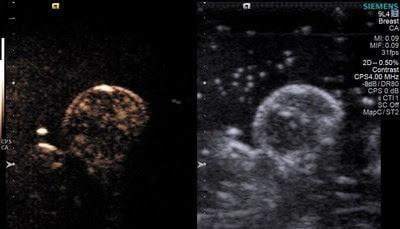

Microbubbles were originally developed to help improve ultrasound imaging. However, being able to "pop" oxygen-filled microbubbles within tumors using beams of ultrasound presented researchers with an opportunity. Most solid tumors are oxygen-deficient, in part because they quickly outgrow the supply of oxygen-carrying blood vessels that can penetrate the tumor mass. That lack of oxygen also makes tumors more resistant to radiation, which is why trying to flush tumors with oxygen became such a prized goal in the field.

In this study, Eisenbrey and colleagues showed that popping the microbubble with ultrasound immediately prior to radiation treatment could triple sensitivity of the cancer to radiation. It also nearly doubled the survival times in mice from 46 days with placebo, nitrogen-filled microbubbles, to 76 days with oxygen-filled microbubbles.

Radiation therapy works by creating oxygen – and other – free radicals in tumors, out of the oxygen present in the tissues. But when those oxygen levels are low, the free radicals produced by radiation therapy are also lower, offering less therapeutic benefit. With this approach, microbubbles are delivered to the general blood flow via intravenous injection, but are popped locally raising the oxygen level only in the tumor. Interestingly, the investigators showed that oxygen increased throughout the cancer mass, even in areas that did not have direct access to blood vessels.